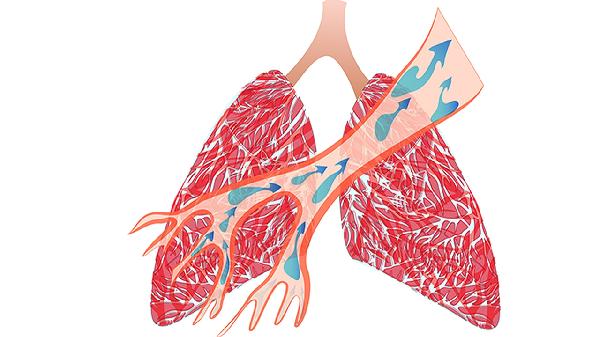

布地奈德福莫特罗粉吸入剂为糖皮质激素与长效β2受体激动剂的复合制剂,适用于中重度慢阻肺稳定期治疗。布地奈德可减轻气道炎症,福莫特罗能扩张支气管,改善气流受限。常见不良反应包括声音嘶哑、口腔念珠菌感染,使用后需漱口以减少局部副作用。

沙美特罗替卡松粉吸入剂同样为复合制剂,适用于慢阻肺合并频繁急性加重的患者。沙美特罗通过松弛支气管平滑肌缓解呼吸困难,替卡松可抑制气道炎症反应。需注意该药可能引起心悸、头痛等不良反应,心血管疾病患者需谨慎使用。

噻托溴铵粉吸入剂属于长效抗胆碱能药物,通过阻断M3受体实现支气管扩张作用,适用于慢阻肺的长期维持治疗。该药每日一次使用方便,但可能引起口干、便秘等抗胆碱能副作用,青光眼患者禁用。